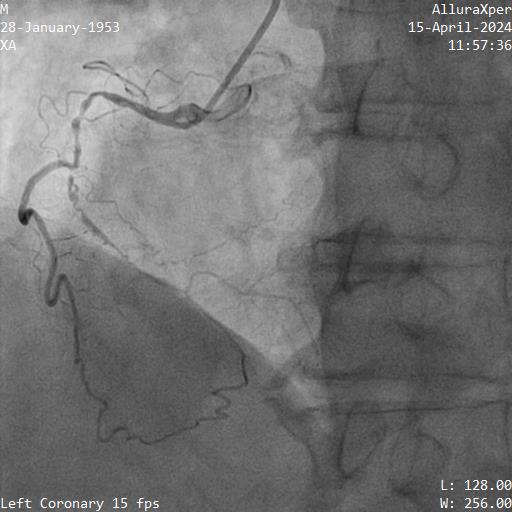

Relevant Catheterization Findings

1. LMT was normal

2. Proximal LAD had a 70-80% stenosis, mid LAD had myocardial bridging. LAD supplied septal collateral (CC) to distal PDA

3. Proximal LCX artery had a 90% stenosis

4. Proximal RCA was diffuse disease 70-80%, mid to distal RCA was a CTO. Ipsilateral CC from marginal to PDA

SYNTAX I score: 28 CABG was offered but patient declined.

PCI was performed for LCX with biolimus eluting stent (BES) 2.5x30mm and LAD with BES 3.0x29mm

He was scheduled for stage PCI RCA CTO 2 months later.